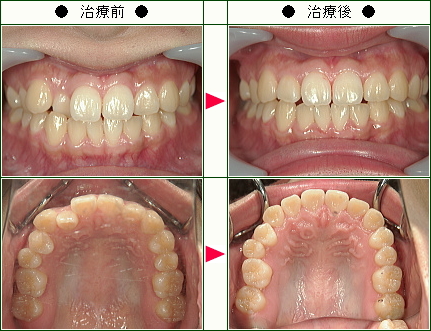

☆歯のデコボコ矯正症例(M.Y様 26歳 男性)